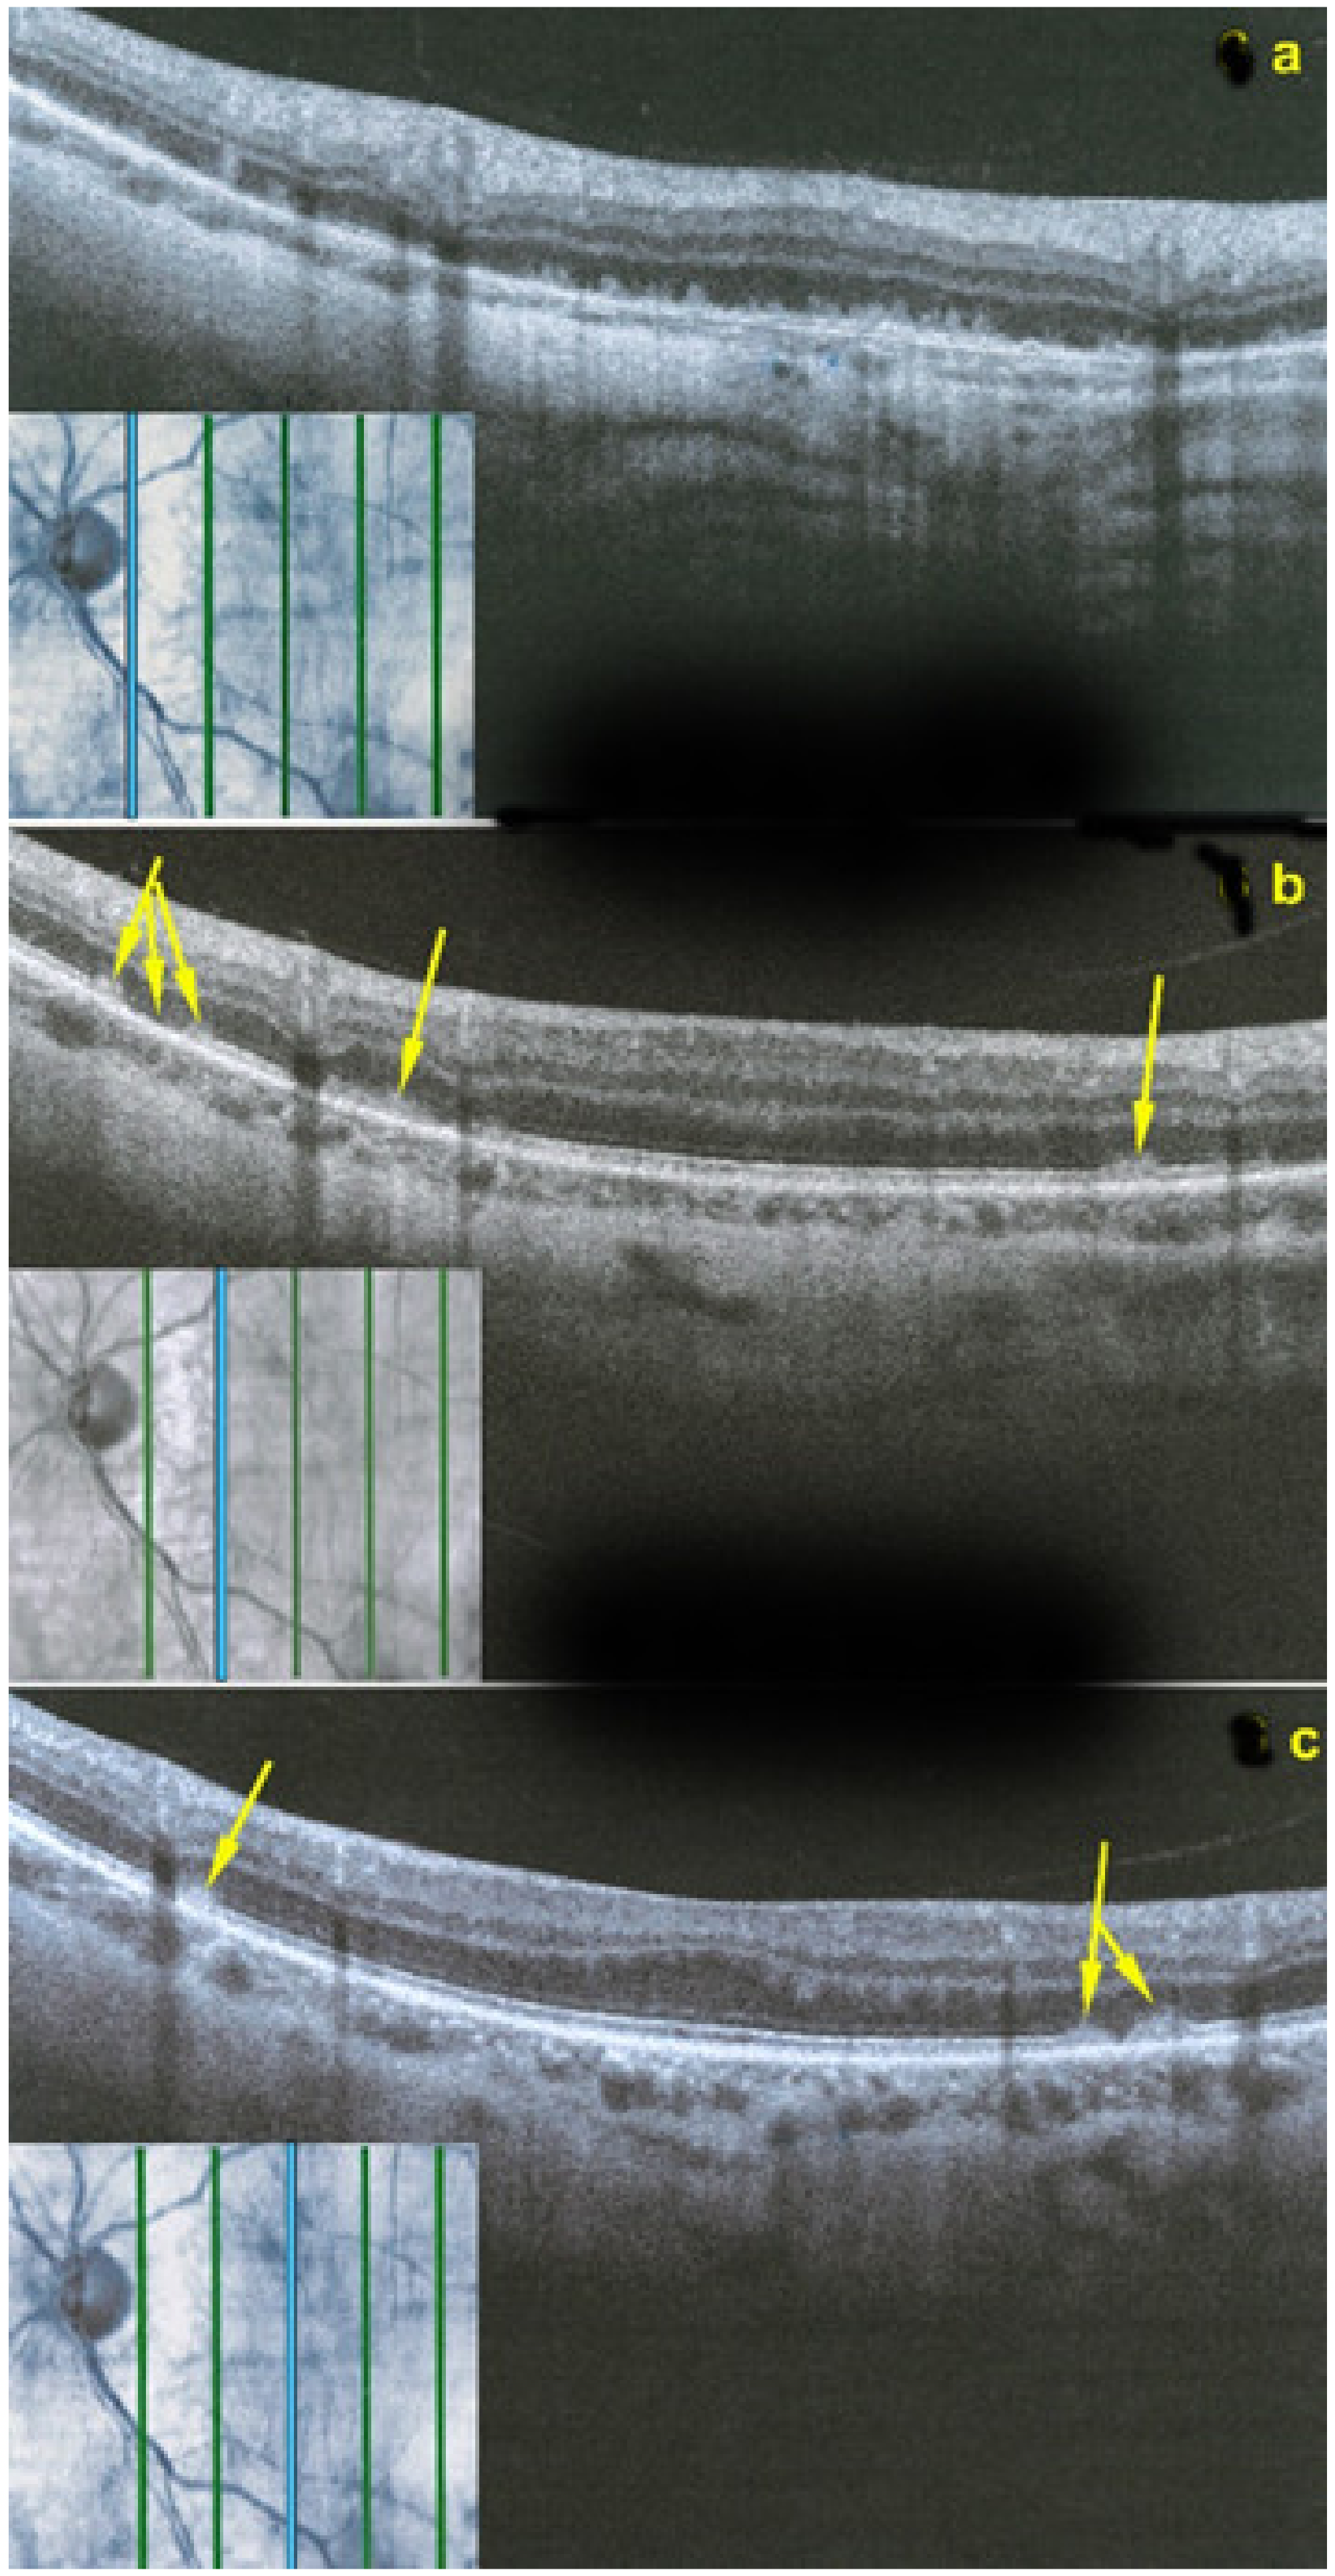

SD-OCT is very helpful as in all other PICCPs. In MFC, OCT pictures show that the degree of repercussion of choriocapillaris non-perfusion on the outer retina and even inner retina is much more pronounced in active phases of MFC when compared to MEWDS or APMPPE/AMIC. This seems to indicate that larger choroidal vessels seem to be involved, as suggested by the only histopathological report available [56]. It is understandable that OCT findings in MFC and APMPPE/AMIC are similar as it is the same mechanism of choriocapillaris closure ± larger vessels with more or less severe consequences on the retina.

Although treatment is purely empirical, aggressive inflammation suppressive treatment associating corticosteroids and non-steroidal immunosuppressive agents can be recommended in case of newly diagnosed active disease or reactivation of MFC. Monitoring of therapy is best done by ICGA, which is the most sensitive modality to detect activity showing progression or regression of hypofluorescent areas [30]. BAF monitoring gives similar information for the follow-up of lesions and has the advantage of not being invasive, (Figure 18, Figure 19, Figure 20 and Figure 21) corresponding to loss of outer segments of photoreceptors visible on SD-OCT (Figure 22)

SD-OCT is useful to follow the borders of the lesions showing the condition of the different retinal layers often thickened by retinal oedema with hyperreflective accumulations in the outer retina with disruption of outer retinal layers. OCTA gives information on the vascular/choriocapillaris drop-out (Figure 25).